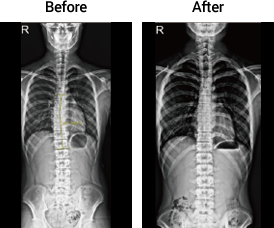

측만증

18세 여성